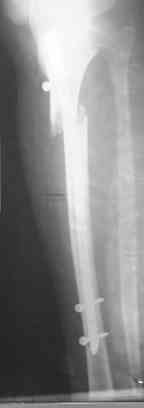

Интрамедуллярный остеосинтез. Как избежать смещение? |

Была прооперирована девушка 17 лет и получена такая Ro-картина.

На сколько критично подобное смещение,

каких последствий можно ожидать и как его упреждать а дальнейшем?

В клинике отсутствует ЭОП!